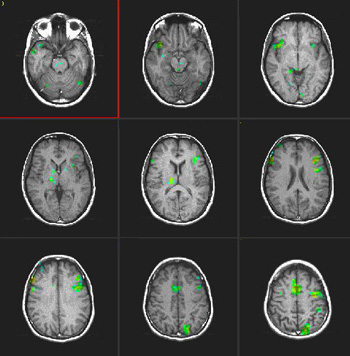

Verbal Comprehension

| Subject | Right-handed volunteer, 32 year-old-man | ||||||

| Paradigm | ON: Listening to a story OFF: Concentrate on the back ground noise | ||||||

| Images | ![]() | ||||||

| Activation | Left hemisphere activation is clearly greater. The activation is in the following areas: Broca's (image 5), Wernike's (images 4 and 5), left supramarginal gyrus (heteromodal associative area, in image 5), left motor and premotor strip. The primary auditory areas are also activated predominantly on the left. |